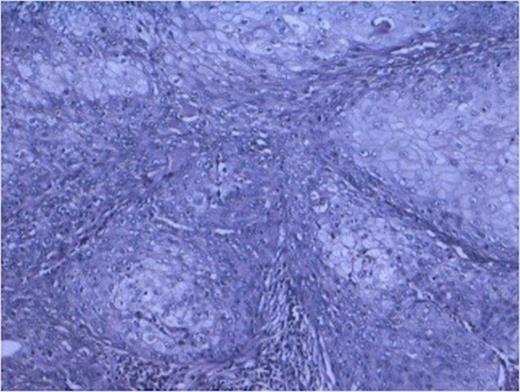

Cyst lined by metaplastic epithelium with focus of malignant squamous cell. (100x H and E stain)

Histopathology from solid portions in pelvis region showed features of moderately differentiated squamous cell carcinoma (Fig 3). The tumor was not involving retroperitoneal soft tissue including renal vessels, Gerota’s fascia and lymph nodes.